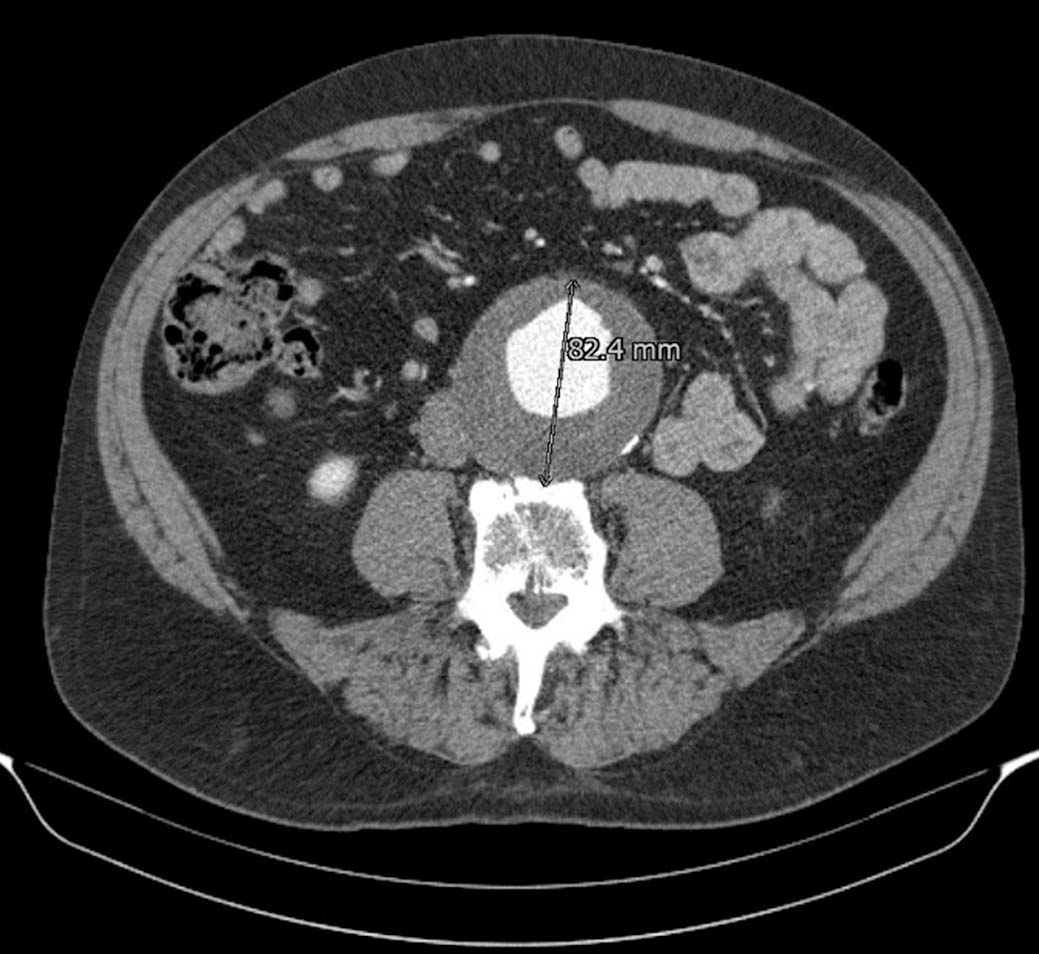

Een snelgroeiend aneurysma van de buikaorta

Soms wordt op een echo of CT van de buik een aneurysma aortae abdominalis (AAA) ontdekt. Vaak gebeurt dat in een ziekenhuis. De radioloog vermeldt die toevalsbevinding meestal wel in de brief aan de huisarts, maar als het AAA ‘klein’ is, wordt meestal niet vermeld dat follow-up geïndiceerd is. Die controle kan echter van levensbelang zijn.